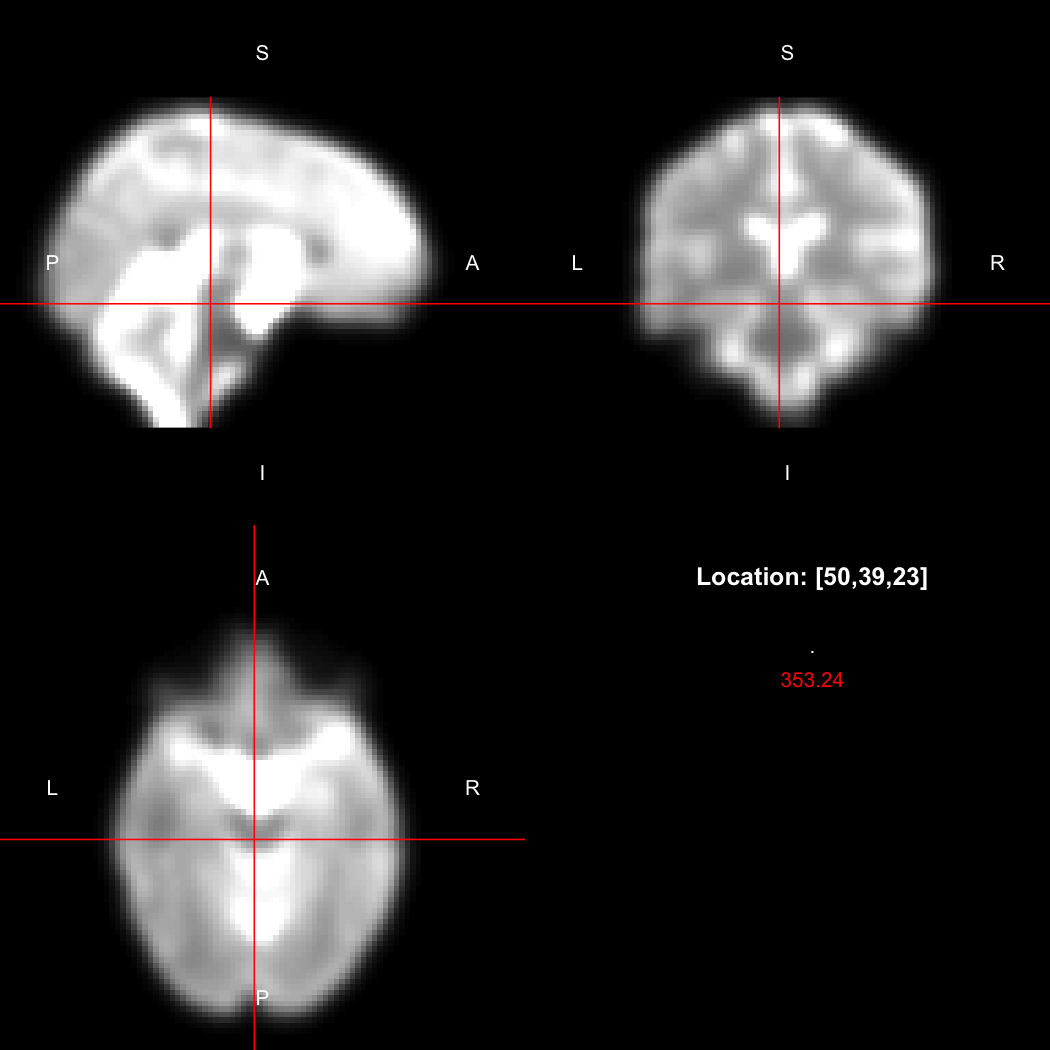

image <- readNifti(system.file("extdata", "example.nii.gz", package="RNifti"))We can also use the RNifti image viewer to visualise the

image.

view(image)